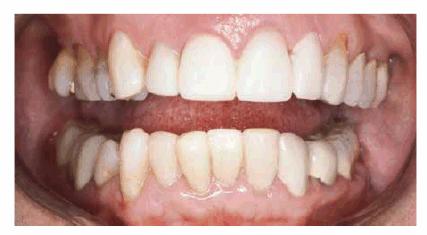

Age and dysfunctional habits can contribute to severe wear over the years. Figures 29-10A, and 29-10B demonstrate evidence of bruxism in an 86-year-old

woman who had been advised to wear a bite guard when she was in her mid 50s.

She disappeared from the practice and returned 30 years later demonstrating

severe wear, loss of vertical dimension, loss of masticatory function, and

temporomandibular pain. More importantly, she was embarrassed by her smile. Her

treatment plan consisted of a temporary crown and bridge to restore vertical

dimension and comfort. She was subsequently treated months later with fixed prosthodontics

using metal-ceramic restorations (Figure 29-10C). She regained much of her self-confidence, as

well as masticatory function, following the esthetic reconstruction of the

maxillary arch (Figure 29-10D) and planned to restore the lower arch.

Figure 29-10A: This lady presented with a severe bruxism habit that resulted in virtually all of her maxillary teeth being hidden when she smiled.

Figure 29-10B: Although she was advised more than 30 years previously to wear a night guard, she chose not to do so.

Figure 29-10C: Crown lengthening followed by prosthodontic reconstruction helped to recreate her smile. The next step is for her to rebuild the mandibular arch.

Figure 29-10D: The reconstructed teeth of this 88-year-old lady now enhance her smile.